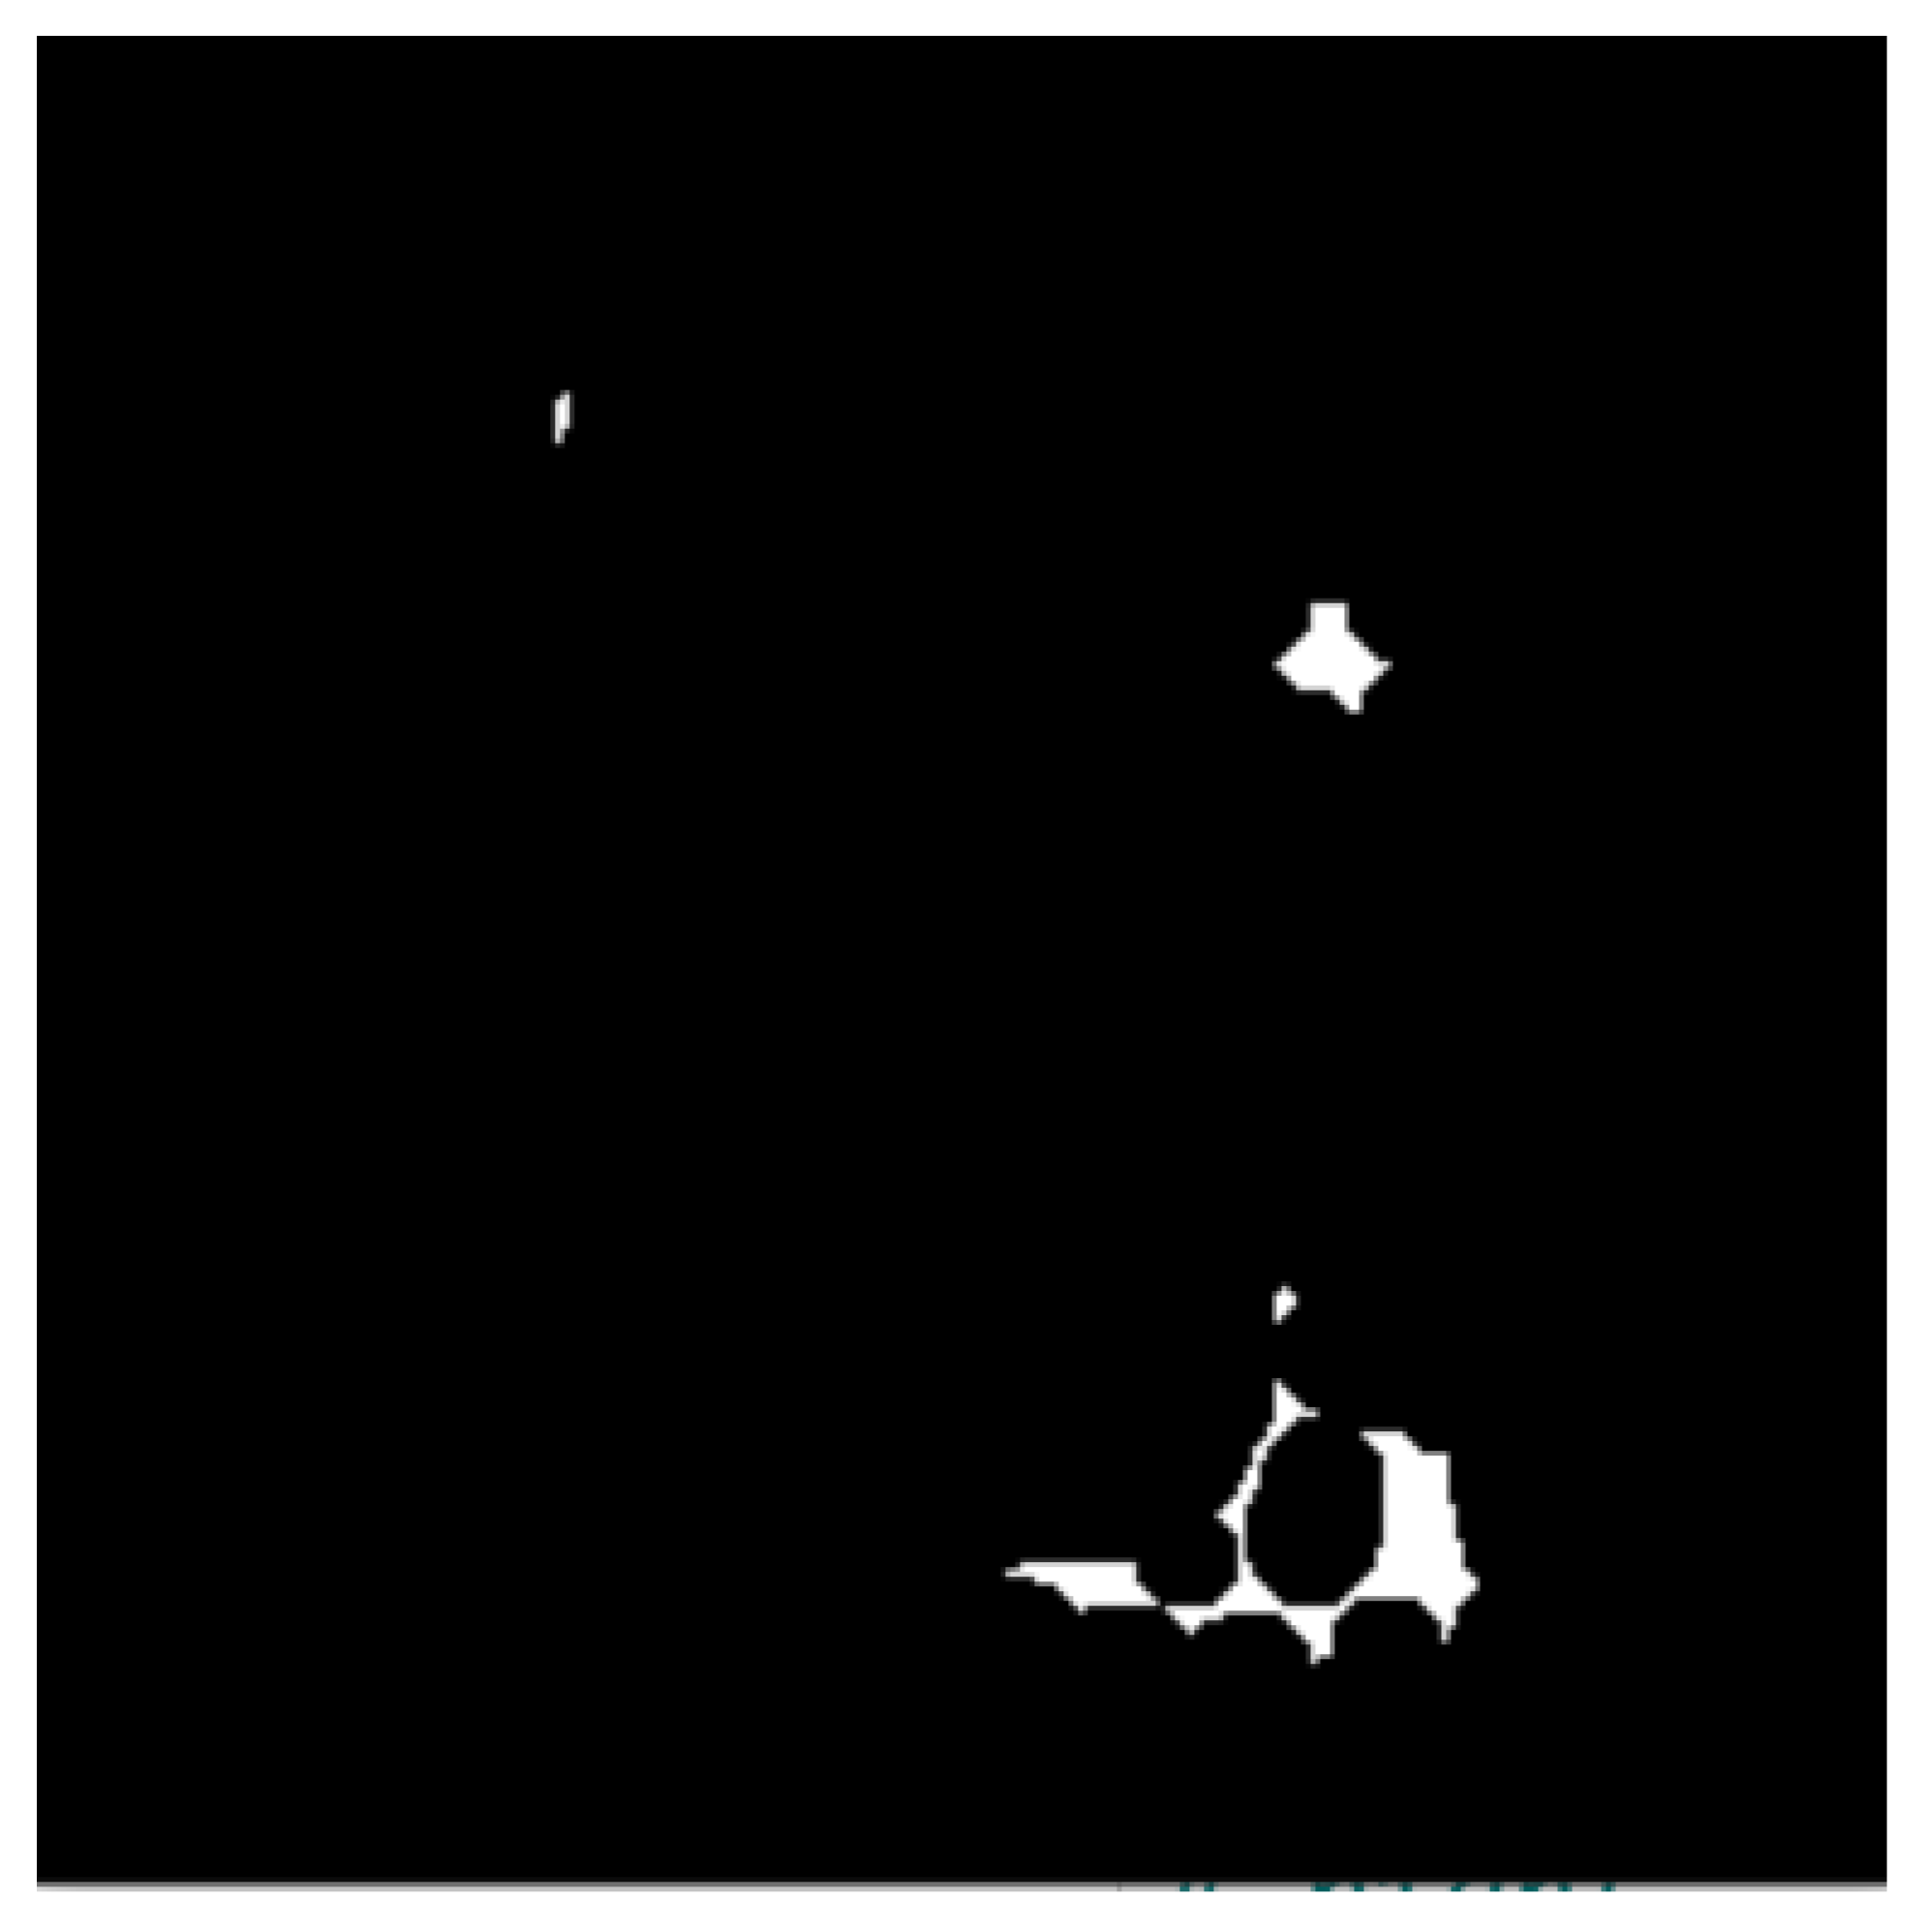

- The use of the connected component analysis method to group components with similar characteristics into binary masks that assist in separating overlapping and non-overlapping objects, thus avoiding over-segmentation.

- The binary masks from the connected component analysis method further aid in addressing the inaccurate segmentation of the image boundaries of intersecting objects, which is common with the active contours method. The proposed method clearly distinguishes the different ROIs from each other, clearly isolating and segmenting the cancerous lesions as visually documented in Section 3 and Section 4.

2.3.1. Connected Component Analysis

2.3.2. Active Contours Segmentation